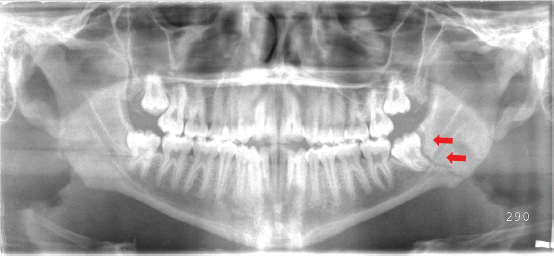

Preoperative examination should include a thorough assessment of occlusion, the dentition, and fracture mobility with bimanual manipulation. The function of the mental nerve should be assessed as well, as any fracture crossing the inferior alveolar canal can result in neurosensory deficits in the lower lip and chin. Although computed tomographic (CT) imaging is standard in facial fractures, most mandibular injuries are adequately assessed with a panoramic x-ray (Panorex) (Figure 14.1) and an anteroposterior (AP) view.